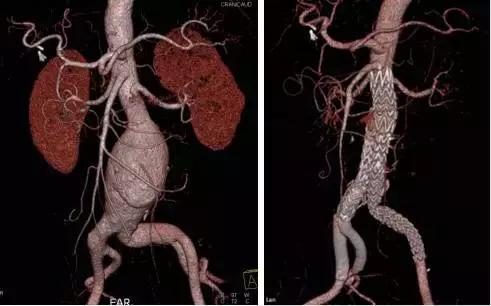

第三阶段:1991-目前,AAA的腔内修复术。1991年Parodi首次报道腔内移植物治疗AAA,1994年Yusuf首次报道分叉型支架移植物治疗AAA,1997年国内也开始了此类手术的临床应用,标志着AAA的手术治疗逐渐进入了腔内治疗的时代。

我们解放军306医院血管外科于2004年初成功实施了第一例AAA的腔内修复术,此后至目前取得了AAA连续腔内治疗100例无死亡和重大并发症的良好成绩。由于腔内治疗的微创性、无需开腹、局麻下即可完成,恢复快、次日下地、一周内可出院,尤其适合高龄和有各种慢性合并症的患者。目前此类手术在国内外逐渐成为主流的治疗方案。

目前,AAA的腔内治疗在3D打印技术辅助、体外开窗技术、烟囱技术、潜望镜技术、一体式分叉型支架使用、去分支杂交手术技术等领域还在不断探索,有望进入AAA完全腔内治疗的新时代。